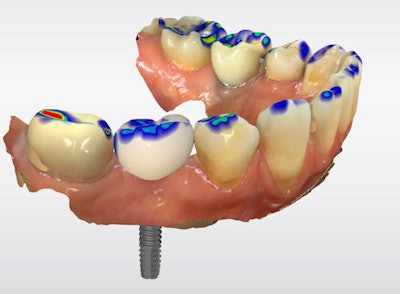

The definitive crown was then designed in CEREC software (Figure 4) using virtual articulation and occlusal analysis (Figure 5) and verified in a full-arch digital view for occlusal harmony (Figure 6). Milling was completed using CEREC Primemill with a Katana Zirconia One for Implant block, producing excellent marginal adaptation and lifelike translucency (Figure 7).

Figure 5: Virtual articulation and occlusal analysis.